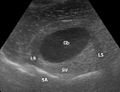

Ultraschall-Aufnahme der Gallenblase -